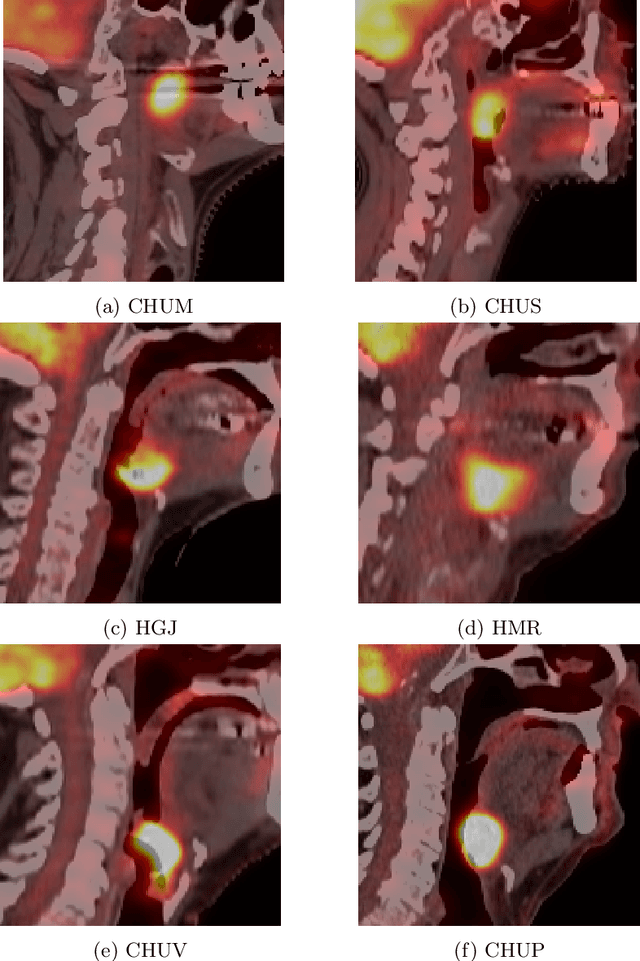

Abstract:This paper presents an overview of the second edition of the HEad and neCK TumOR (HECKTOR) challenge, organized as a satellite event of the 24th International Conference on Medical Image Computing and Computer Assisted Intervention (MICCAI) 2021. The challenge is composed of three tasks related to the automatic analysis of PET/CT images for patients with Head and Neck cancer (H&N), focusing on the oropharynx region. Task 1 is the automatic segmentation of H&N primary Gross Tumor Volume (GTVt) in FDG-PET/CT images. Task 2 is the automatic prediction of Progression Free Survival (PFS) from the same FDG-PET/CT. Finally, Task 3 is the same as Task 2 with ground truth GTVt annotations provided to the participants. The data were collected from six centers for a total of 325 images, split into 224 training and 101 testing cases. The interest in the challenge was highlighted by the important participation with 103 registered teams and 448 result submissions. The best methods obtained a Dice Similarity Coefficient (DSC) of 0.7591 in the first task, and a Concordance index (C-index) of 0.7196 and 0.6978 in Tasks 2 and 3, respectively. In all tasks, simplicity of the approach was found to be key to ensure generalization performance. The comparison of the PFS prediction performance in Tasks 2 and 3 suggests that providing the GTVt contour was not crucial to achieve best results, which indicates that fully automatic methods can be used. This potentially obviates the need for GTVt contouring, opening avenues for reproducible and large scale radiomics studies including thousands potential subjects.